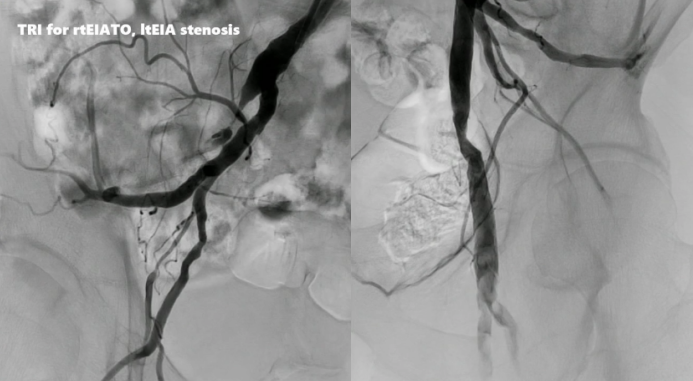

病例一:右侧髂外动脉完全闭塞及左侧髂外动脉狭窄

1、造影显示患者右侧髂外动脉完全闭塞及左侧髂外动脉狭窄。

2、导丝通过后,使用6x40mm SABERX RADIANZ®球囊进行预扩张,植入8x100mm S.M.A.R.T. RADIANZ®支架,并使用6x40mm SABERX RADIANZ®球囊进行后扩张,造影结果满意。

3、随后使用JR4导管将鞘管引导至左侧,进行扩张和后扩张,最终造影结果成功,由此可见,经桡动脉入路可一次性处理双侧病变。